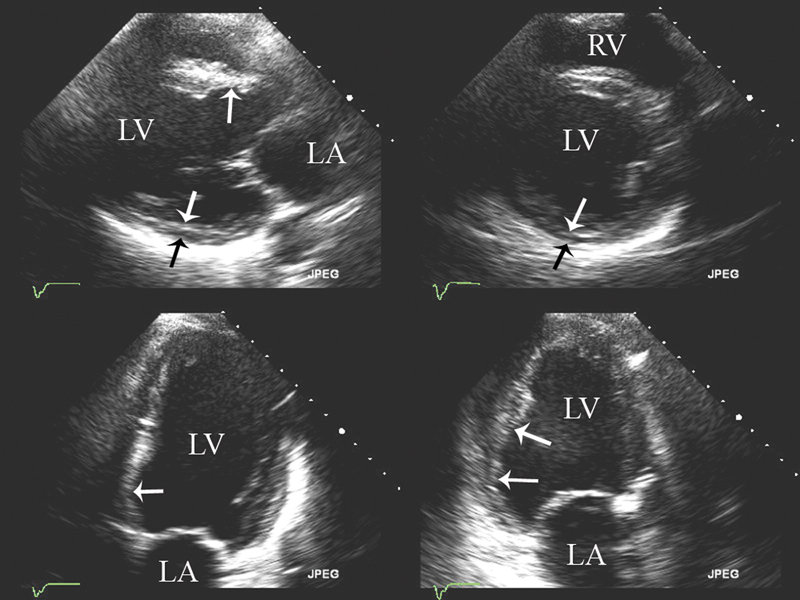

فحوصات تشخيصية لبعض امراض القلب والشرايين التاجية